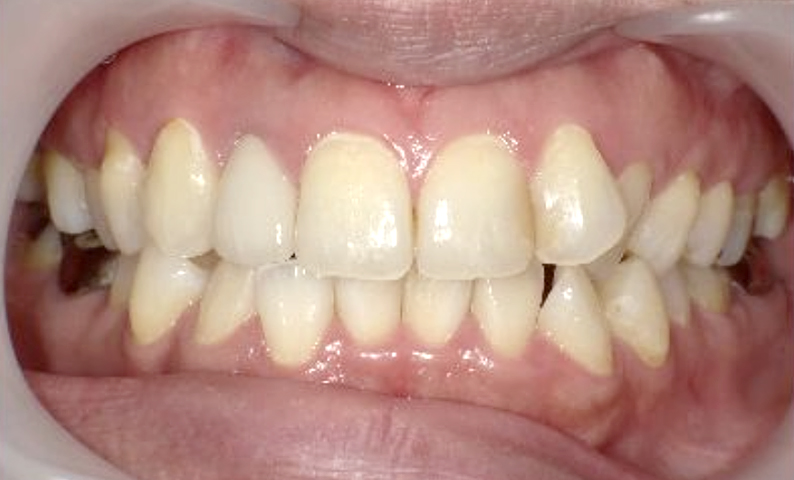

症例_022 上下顎の部分矯正

治療期間:9ヶ月金額:51万円+税女性前歯のガタガタ八重歯

| Before | After |